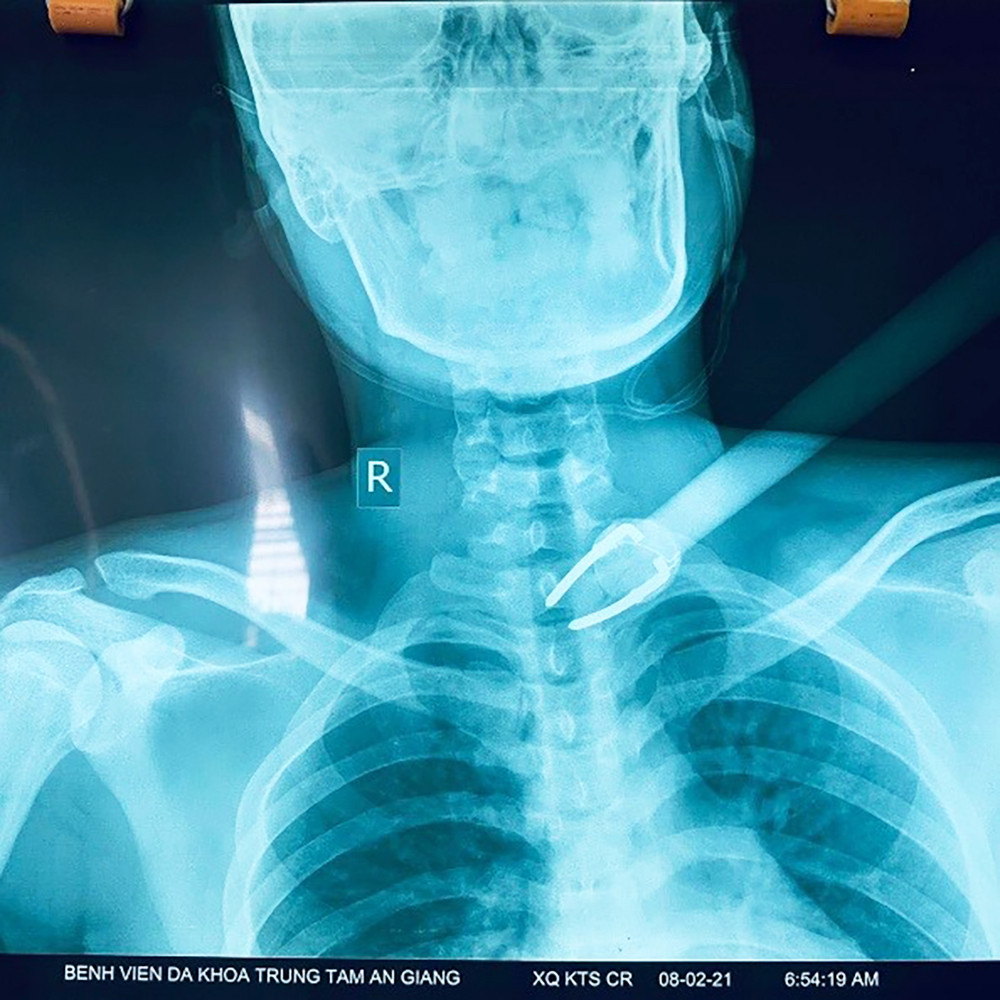

Đuổi theo kẻ trộm chó, nam sinh viên bị bắn tên xuyên cổ ảnh 1Mũi tên được lấy ra từ người nạn nhân. Ảnh: Báo An Giang.

Đuổi theo kẻ trộm chó, nam sinh viên bị bắn tên xuyên cổ ảnh 2Mũi tên được lấy ra từ người nạn nhân. Ảnh: Báo An Giang.

Sau 3 giờ, ê-kíp phẫu thuật gồm các bác sĩ ngoại thần kinh lồng ngực, tai -mũi- họng, gây mê hồi sức đã phẫu thuật lấy “dị vật cực kì nguy hiểm vùng cổ” bệnh nhân D. là mũi tên dài 50cm, với phần mũi kim loại chia làm 2 ngàm dài 8cm, có mũi chĩa 2mm đường kính ở cổ bệnh nhân. Các bác sĩ tham gia phẫu thuật cho biết, mũi tên đâm xuyên vào vùng cơ đến tận đốt sống cổ C7-D1 em D.

Tuy nhiên, may mắn nó chỉ gây bóc tách cơ vùng cổ, ngực, mà không gây thủng hay tổn thương “mạch máu - thần kinh - khí quản - thực quản”. Bởi, chỉ cần tổn thương một trong 4 vị trí trên, bệnh nhân có thể tử vong ngay lập tức hoặc bị di chứng tàn phế nặng nề về sau gây giảm chất lượng cuộc sống.